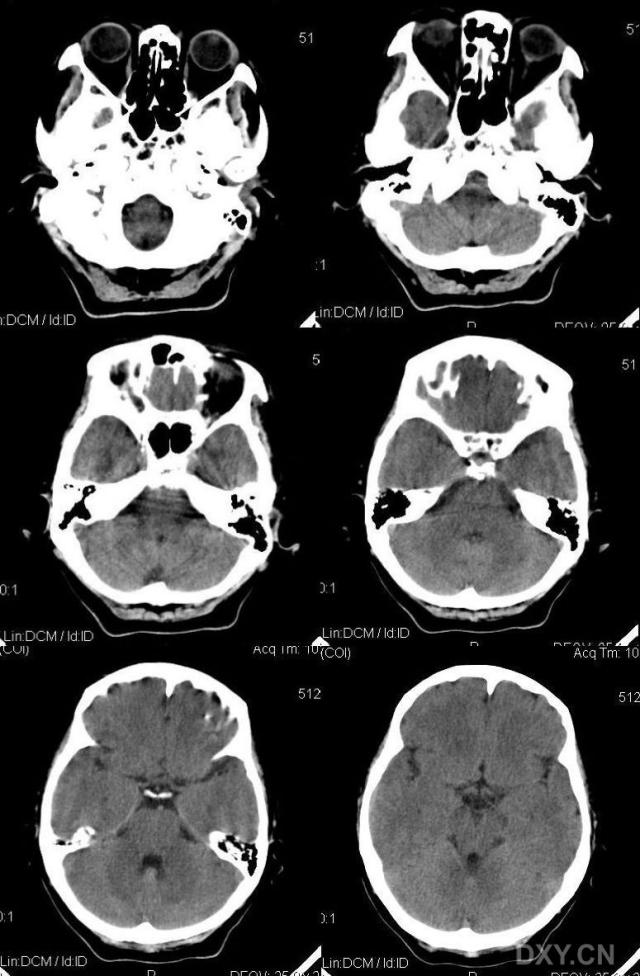

标题: CT11931:请看看有无异常!!

女性,62岁.头顶部不适,自述"头顶发凉"多年.

颅内无异常,骨窗呢?

脑内未见异常,顶部头皮下怎么有多个点状高密度影?重建个骨窗吧!

头皮下多个点状高密度影,ct值220hu左右,考虑是什么东西

头顶部皮下软组织内多个点状高密度影,ct值220hu左右,考虑是什么东西???

颅内ct平扫未间异常。顶部皮下可见多发小点状钙化影,病人无个伤排除异物情况下,考虑囊虫病后遗改变,建议上传软组织窗。

颅顶部皮下多发小结节状高密度影,边缘锐利;颅内未见异常,结合有头顶发凉病史,考虑多发静脉石可能。

颅脑ct轴位平扫颅内未见明确异常。顶部皮下可见多发小点状高密度影,首先排除异物的可能

患者没有明显外伤史,对于囊虫病,我觉的为什么只局限在头顶部皮下,而颅内一切正常。我比较倾向于静脉石可能。